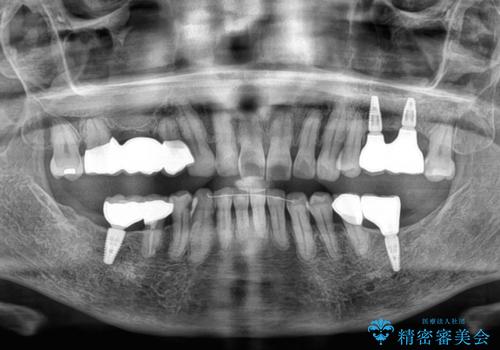

最終的に奥歯はオールセラミッククラウンによる補綴治療を行うこととしました。

治療前は磨き残しが多く見られ、全体的に歯肉が腫れている状態でしたが、抜歯の必要な歯を抜いたことで口腔内の環境が改善され、磨き残しも少なくなってきました。

インプラントにより咬合が回復したことで、治療開始時に認められた上顎前歯の動揺も改善されました。